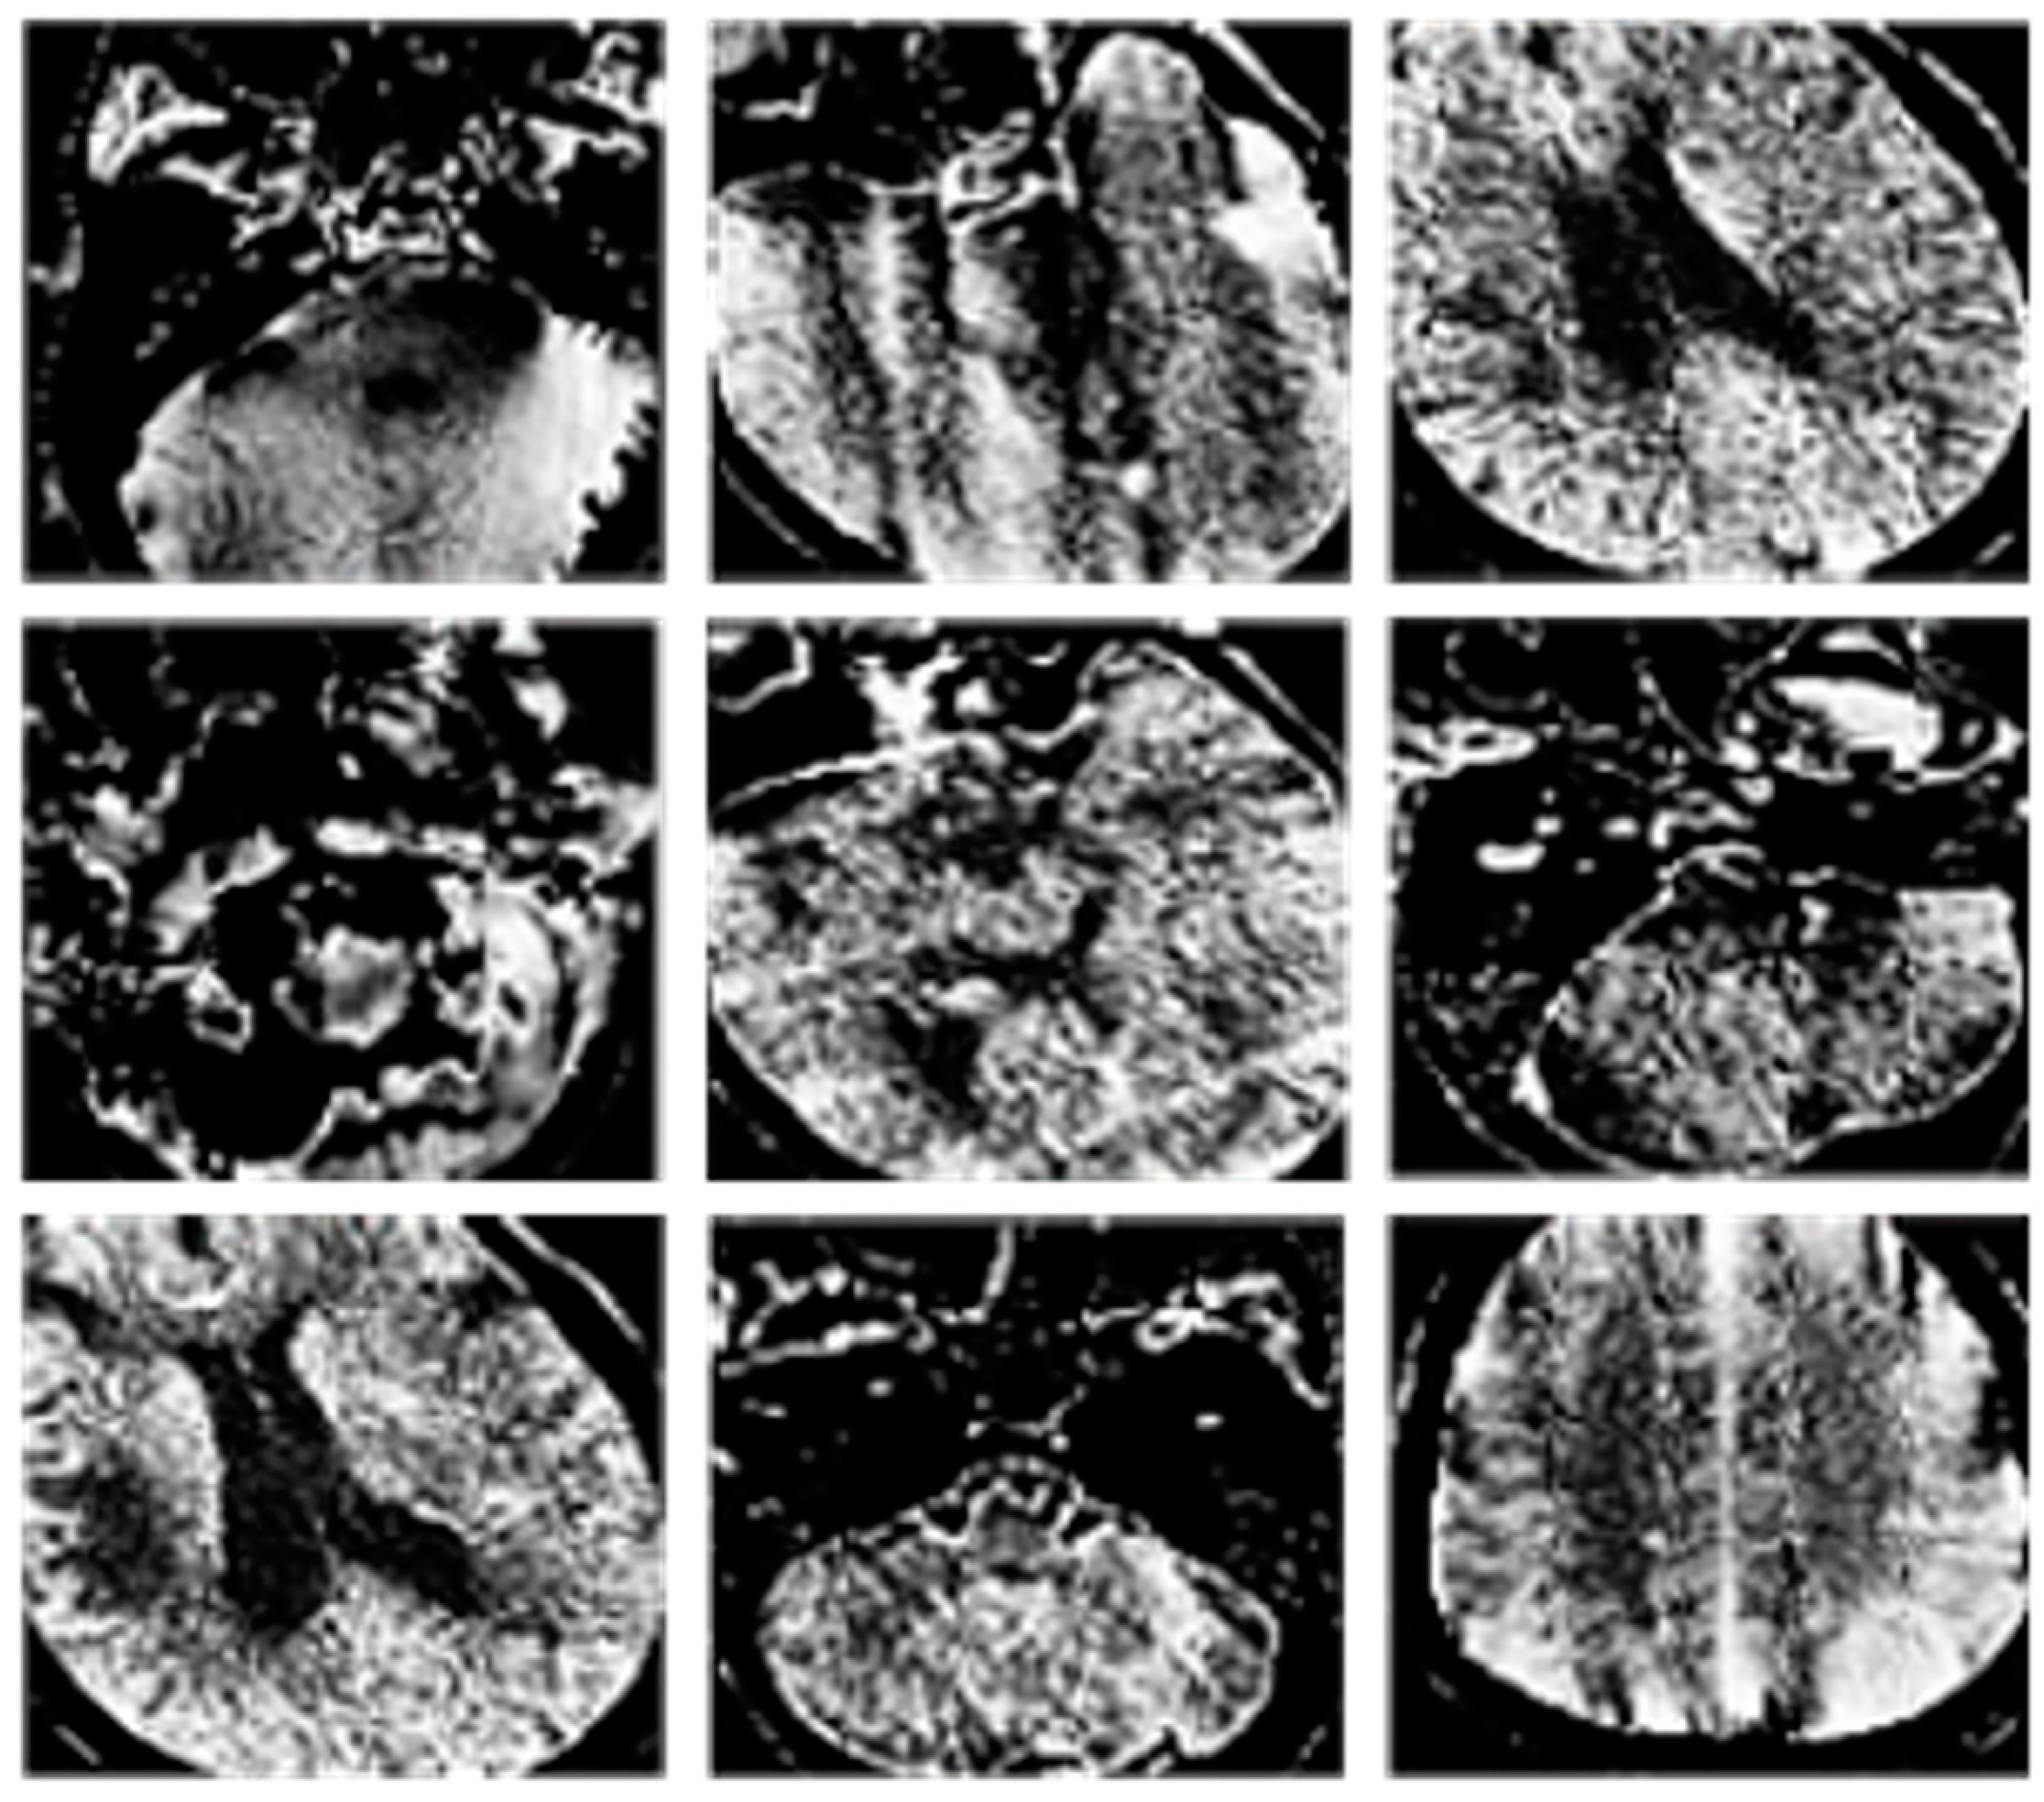

Examples of the classification results are provided in Figure 5 and Figure 6.

Figure 5. Results of CT image classification. In particular, CT images with artifacts.

Figure 6. Results of CT image classification. In particular, CT images without artifacts.